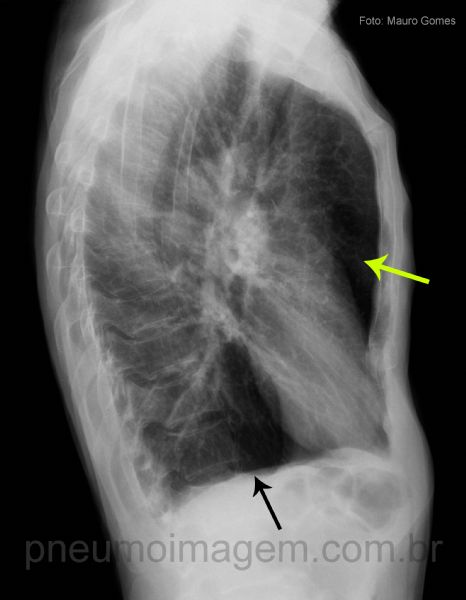

Na incidência em perfil oberva-se o aumento do diâmetro anteroposterior, melhor caracterizado pela presença de ar retroesternal (seta amarela) e infracardíaco. Observe o formato do tórax em tonel. A retificação das cúpulas frênicas pode ser melhor caracterizada nesta incidência (seta preta).

In the profile incidence, the increase of the anteroposterior diameter was observed, better characterized by the presence of retrosternal (yellow arrow) and infracardiac air. Note the chest format in barrel. Rectification of phrenic domes may be better characterized in this incidence (black arrow).

Chaves: AP diameter increased; flat diaphragms (black); retrosternal (yellow) and infracardiac air; barrel chest.